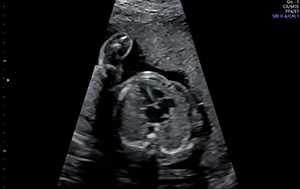

Advanced fetal diagnostic testing can help give your provider the most information possible about your baby’s condition. This can include detailed fetal ultrasounds, MRI, and echocardiograms to monitor and evaluate the baby’s health.

At UR Medicine, we offer advanced fetal diagnostic testing including Level II ultrasound (a detailed view of your baby’s anatomy), fetal echocardiogram, and fetal MRI.

Level II Ultrasound

We are a Level II diagnostic ultrasound unit. Level II ultrasound means that our staff and physicians are qualified to perform and interpret more detailed fetal ultrasounds than general OB/GYN physicians or general radiology offices. At our AIUM accredited ultrasound unit, our team of 14 dedicated obstetrical sonographers are ARDMS certified, having the specialized training to be able to give you more information on complex findings in your baby.